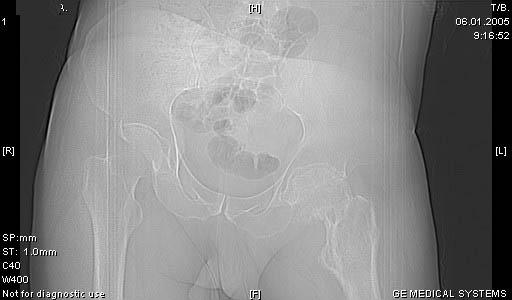

И снова вопрос по эндопротезированию: Пациенту 51 год. Болен с 2000 г, когда отметил умеренные, нараостающие боли в в/3 левого бедра, прогрессирующую контрактуру лев Т/Б сустава.

05.12.04 после падения на бедро боли резко усилились, нога стала неопорной. На рентгенограмме обнаружен патологический перелом шейки бедренной кости. Обследован в отделении костной онкологии. Результат биопсии: асептический некроз проксимального отдела бедренной кости. Вопрос: выбор технологии эндопротезирования - цементная или бесцементная версия. Заранее благодарю! С уважением,А.В.Владзимирский

Про ножку трудно сказать, снимки очень короткие.

Проксимальный отдел бедра не виден достаточно на представленных рентгенограммах; но то, что видно, как раз наводит на мысли о цементной фиксации - цилиндрический канал, измененный calcar, кистозные изменения в области большого вертела и т.д.

Как то очень подозрительно выглядит проксимальный отдел бедра для такого очень простого гистологического заключения. Вы уверены, что гистология настолько благополучна и в каком варианте она выполнялась: пункционная или открытая с забором костного блока? Не уверен на все сто , но область проксимального отдела бедра - одно из излюбленных мест для гигантоклеточной опухоли, которая зачастую озлакочествляется (имел два подобных наблюдения). Из своей практики могу сказать, что, к сожалению, информативность пункционной биопсии не сравнима с открытой техникой. Поэтому прежде чем решать цементный или бесцементный протез использовать, я бы повторил биопсию в сочетании со сканированием скелета, сывороточная щелочная фосфатаза, кальций, фосфор сыворотки, СОЭ, С- реактивный белок,

Soglasen s Евгений И Чекашкин, proximal Femur does not look right. Sarcoma? Pagets, Osteomyelitis?. Technicality of the implantaion will be dependent upon underlying pathology, and the surgeon's level of comfort.

Действительно, проксимальный отдел бедра выглядит подозрительно. По-моему напоминает болезнь Педжета. Кстати, гистологическое заключение в таком случае часто звучит как "хроническое воспаление", "асептический некроз с элементами лейкоцитарной инфильтрации" и т.п. Далеко не все патоморфологи имеют достаточный опыт для дифференцировки костной патологии.